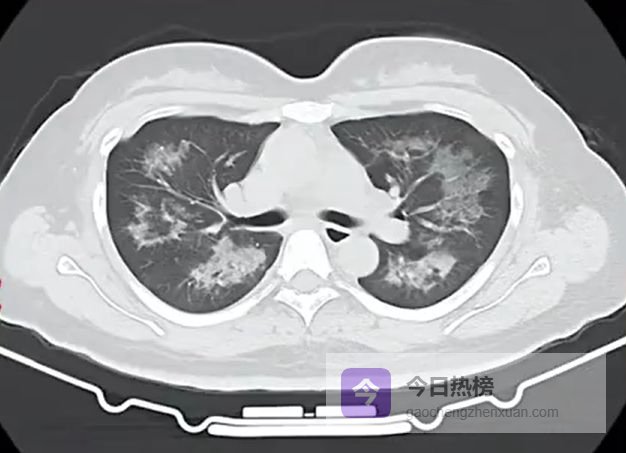

胸部CT进一步显示,她的双肺出现多发斑片状模糊影,被诊断为间质性肺炎。医生判断,病因很可能与她长期接触的某类物质有关。经过反复细致地询问病史,小江才说出自己长期、频繁使用定妆喷雾的习惯。